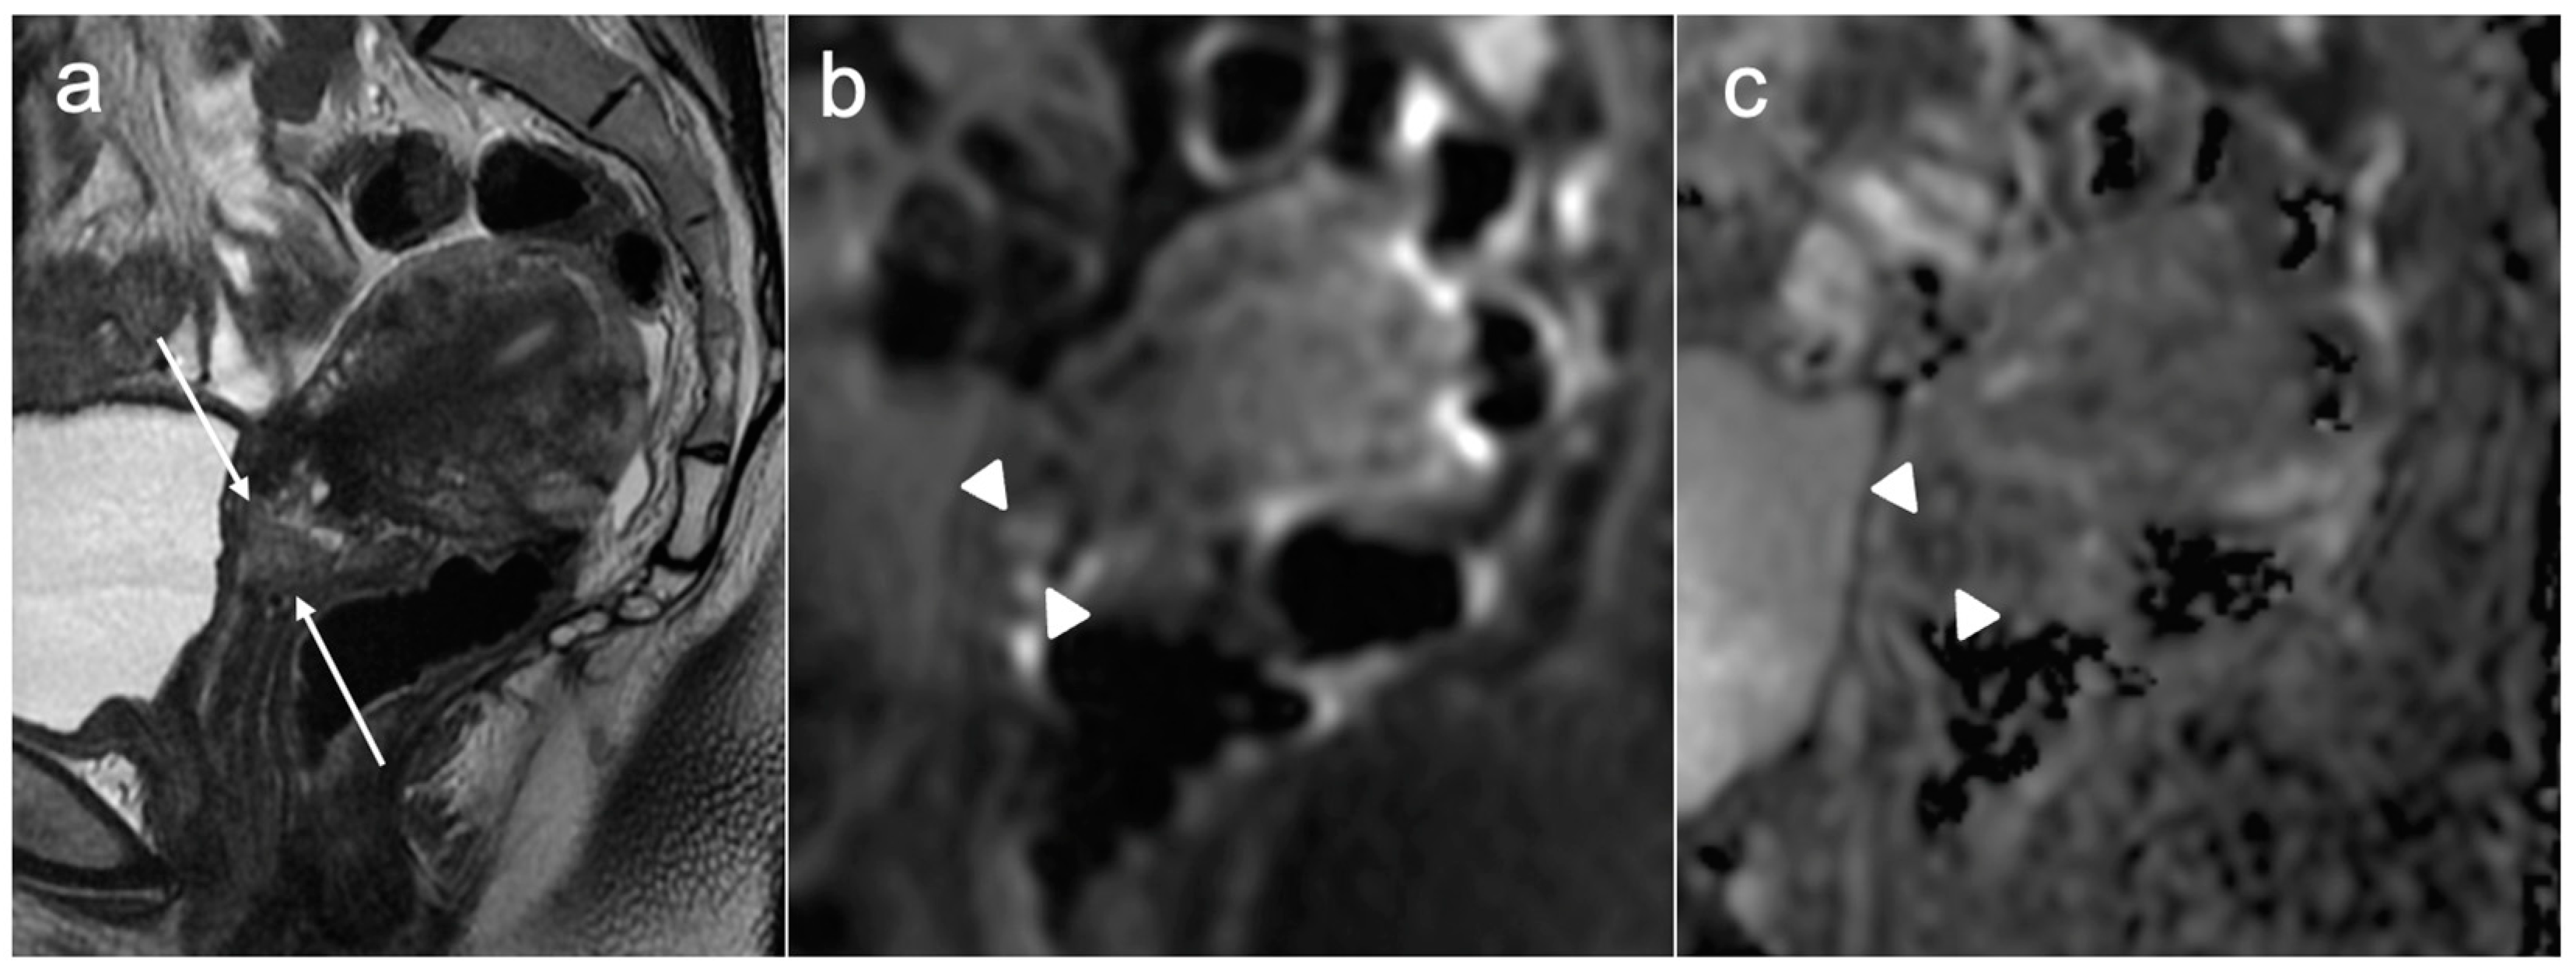

- Avesani, G.; Perazzolo, A.; Amerighi, A.; Celli, V.; Panico, C.; Sala, E.; Gui, B. The Utility of Contrast-Enhanced Magnetic Resonance Imaging in Uterine Cervical Cancer: A Systematic Review. Life 2023, 13, 1368. [Google Scholar] [CrossRef] [PubMed]

- Akita, A.; Shinmoto, H.; Hayashi, S.; Akita, H.; Fujii, T.; Mikami, S.; Tanimoto, A.; Kuribayashi, S. Comparison of T2-weighted and contrast-enhanced T1-weighted MR imaging at 1.5 T for assessing the local extent of cervical carcinoma. Eur. Radiol. 2011, 21, 1850–1857. [Google Scholar] [CrossRef]

| Sagittal and axial oblique DWI and ADC maps (corresponding to sagittal and axial oblique T2WI) | Identifying small isointense tumours, unsuspected bone metastases |